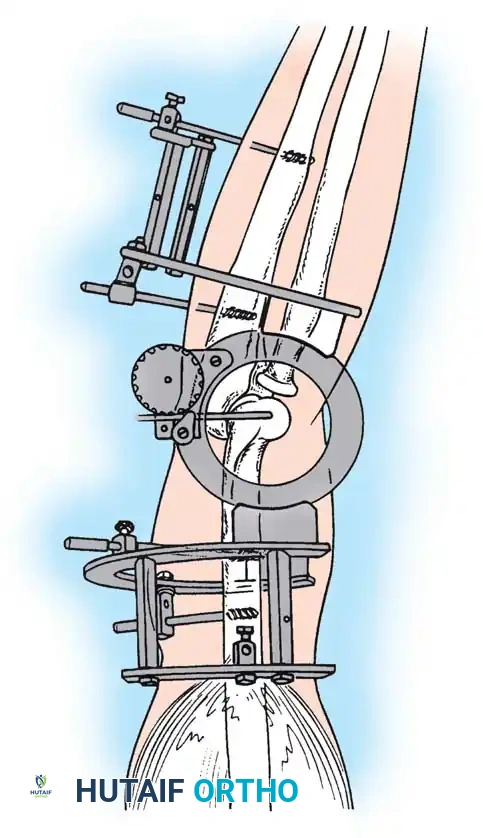

Hinged External Fixation

The current gold standard for managing instability following extensive open reduction is the application of a hinged elbow external fixator. Jupiter, Ring, and Hotchkiss have demonstrated excellent results using hinged fixators to maintain concentric joint reduction, permit early active/passive motion, and enhance muscle-tendon stretching.

Fig. 58-25 Late-discovered medial elbow dislocation managed with open reduction and hinged external fixation without primary ligament repair. (From Hotchkiss RN: Fractures and dislocations of the elbow, 1996.)

Surgical Technique: Compass Hinged Elbow External Fixator (Hotchkiss)

The ulnohumeral articulation is a highly constrained hinge joint. Because only slight movement of the instant center of rotation occurs during flexion and extension, locating the exact rotational axis is the most critical step in applying a dynamic fixator.

Assembly of the Hinge Block

The Compass hinge utilizes a precision worm gear to provide controlled displacement for stretching through extremes of motion.

Fig. 58-27 Design features of the hinged elbow external fixator, noting the built-in 7 degrees of valgus to approximate the distal humerus anatomy.

Preoperative assembly is vital. The hinge block must be configured so the large block sits medially. The differential block height accommodates the average 7 degrees of distal humeral valgus, ensuring the upper ring remains perpendicular to the humerus while the axis of rotation is perfectly aligned.

The Compass hinge arrives assembled for a right arm.

Fig. 58-28A The Compass hinge in its default right arm configuration.

To convert it for a left arm, remove the proximal 5/8-inch ring by loosening the T-bolts. Remove the proximal blocks using a 9/64-inch hex wrench.

Fig. 58-28B Switch the blocks to the opposite wheel, rotating each block 180 degrees so the tilt is reversed.

Resecure the blocks tightly and replace the proximal ring.